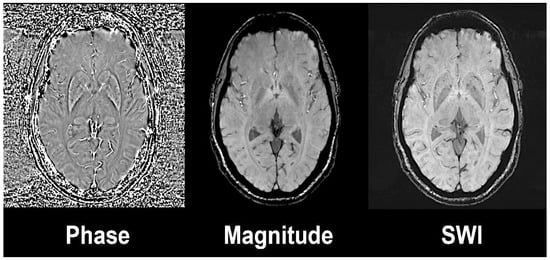

- Haacke, E.M.; Xu, Y.; Cheng, Y.C.N.; Reichenbach, J.R. Susceptibility weighted imaging (SWI). Magn. Reason. Med. 2004, 52, 612–618. [Google Scholar] [CrossRef]

- Deistung, A.; Schweser, F.; Reichenbach, J.R. Overview of quantitative susceptibility mapping. NMR Biomed. 2017, 30. [Google Scholar] [CrossRef] [PubMed]